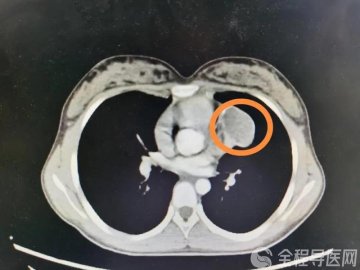

磊磊老是呕吐、拉肚子不止的原因是什么呢?徐州市儿童医院消化科主治医师赵琳琳介绍说,磊磊呕吐、拉肚子就是典型的轮状病毒感染所致。

轮状病毒导致的急性肠炎临床特点很明显:第一个,先呕吐后腹泻;第二个,常常伴有高热、发烧的症状;轮状病毒常常是通过口-粪以及呼吸道传播的;常发于秋季,也称秋季腹泻。

轮状病毒肠炎好发于每年10月至次年2月寒冷的秋冬季节,主要发生于5岁以下儿童,尤其是6个月~3岁的婴幼儿,发病率最高的是6个月~2岁婴幼儿,且最严重。